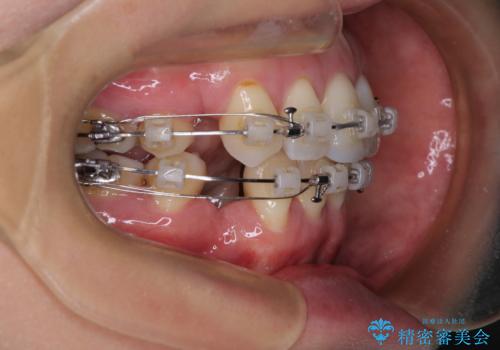

- クリアブラケット

- 2年3ヶ月

- 10-30回